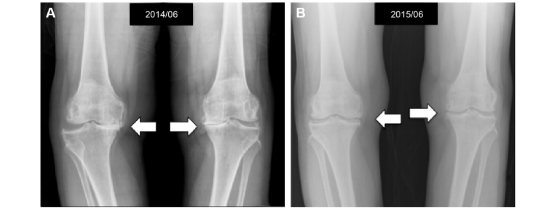

膝关节骨性关节炎(KOA)是常见导致膝关节疼痛和残疾的退行性疾病之一。目前治疗方法主要以缓解疼痛和症状为目的,关节内注射富血小板血浆(PRP)作为一种微创疗法,可安全有效地治疗KOA。PRP内富含多种生长因子,具有促进细胞增殖和胶原合成的作用,能有效修复关节软骨,延缓其退行性改变,近年来在治疗骨关节炎,特别是KOA方面应用广泛。全身振动训练(whole body vibration training, WBVT)作为一种新兴的运动治疗手段逐渐受到关注,该训练方法在康复医学领域应用广泛,有研究证实其有助于改善肌肉骨骼系统疾病(慢性腰痛,膝骨关节炎)和神经系统疾病(脑卒中、脊髓损伤)功能障碍。

图为膝骨关节炎患者注射PRP后膝关节影像学改变。